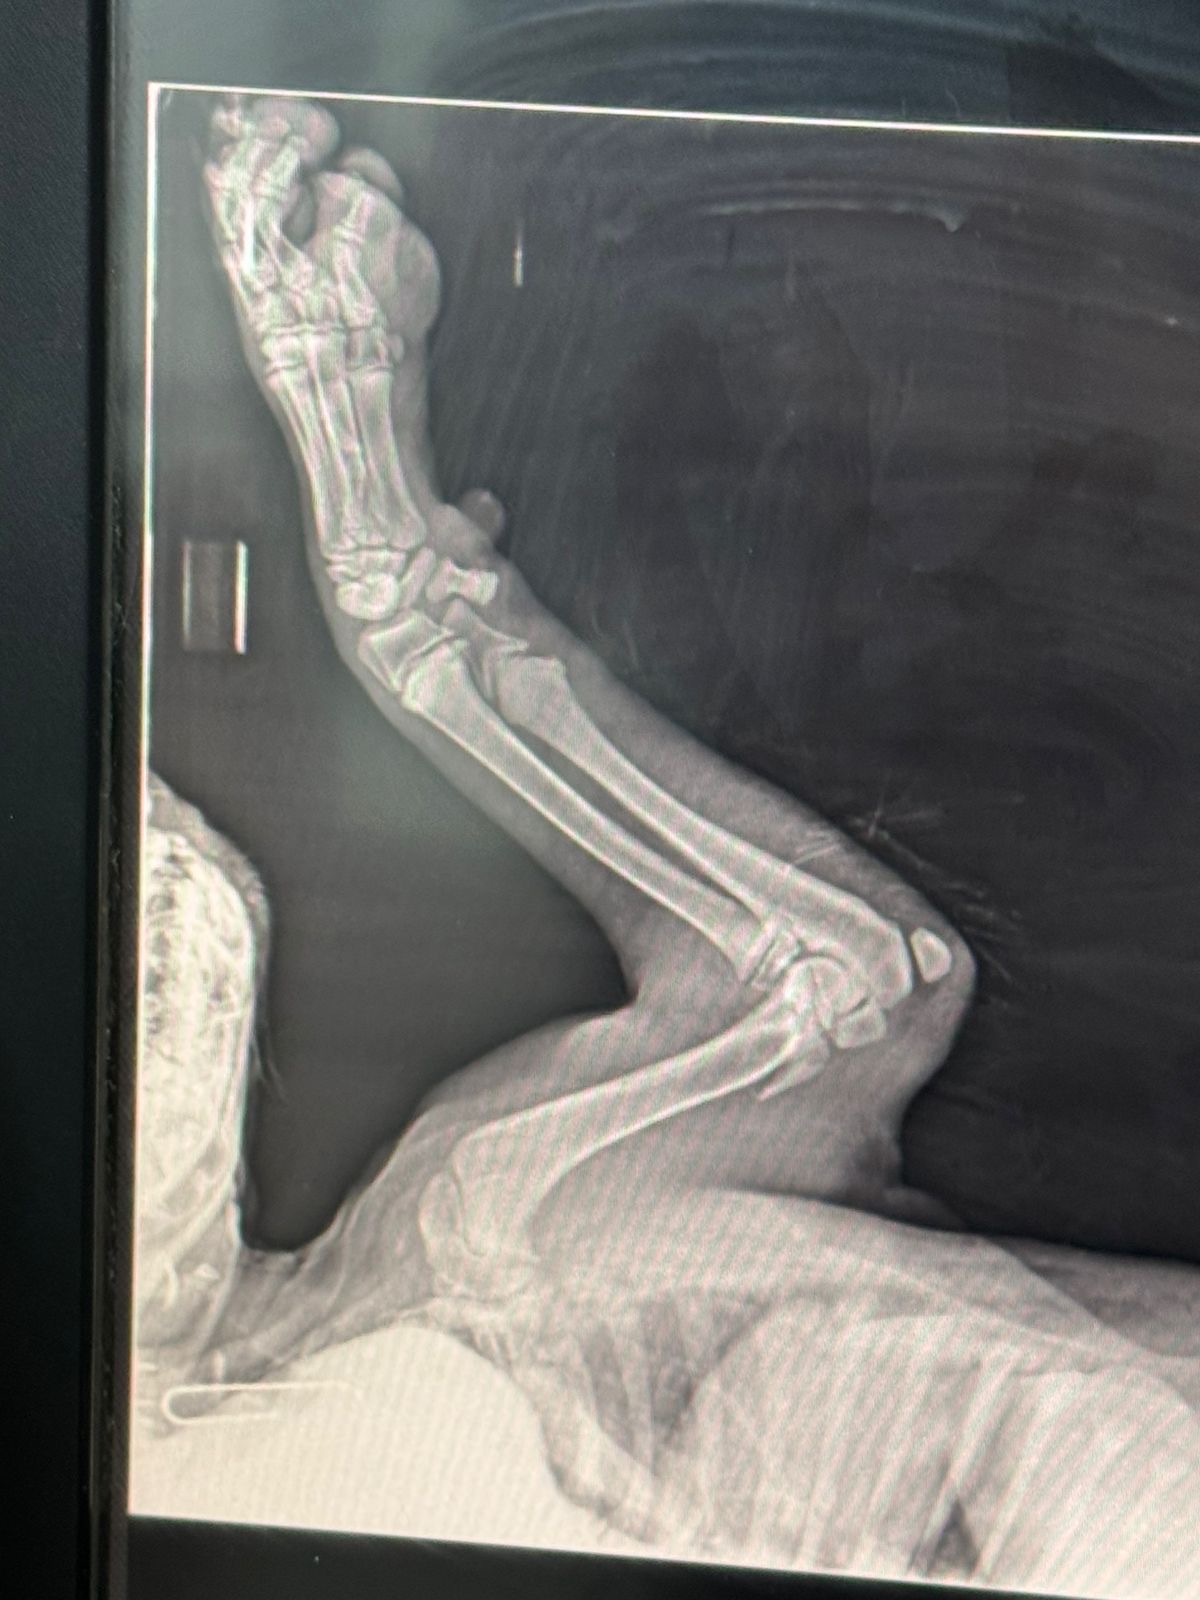

Legend was hit by a car, he had broken front and back legs. His recovery was long after 2 surgeries. He was rescued from the Chouf, laying on the side of the road under the rain. DOB: 24/8/2024